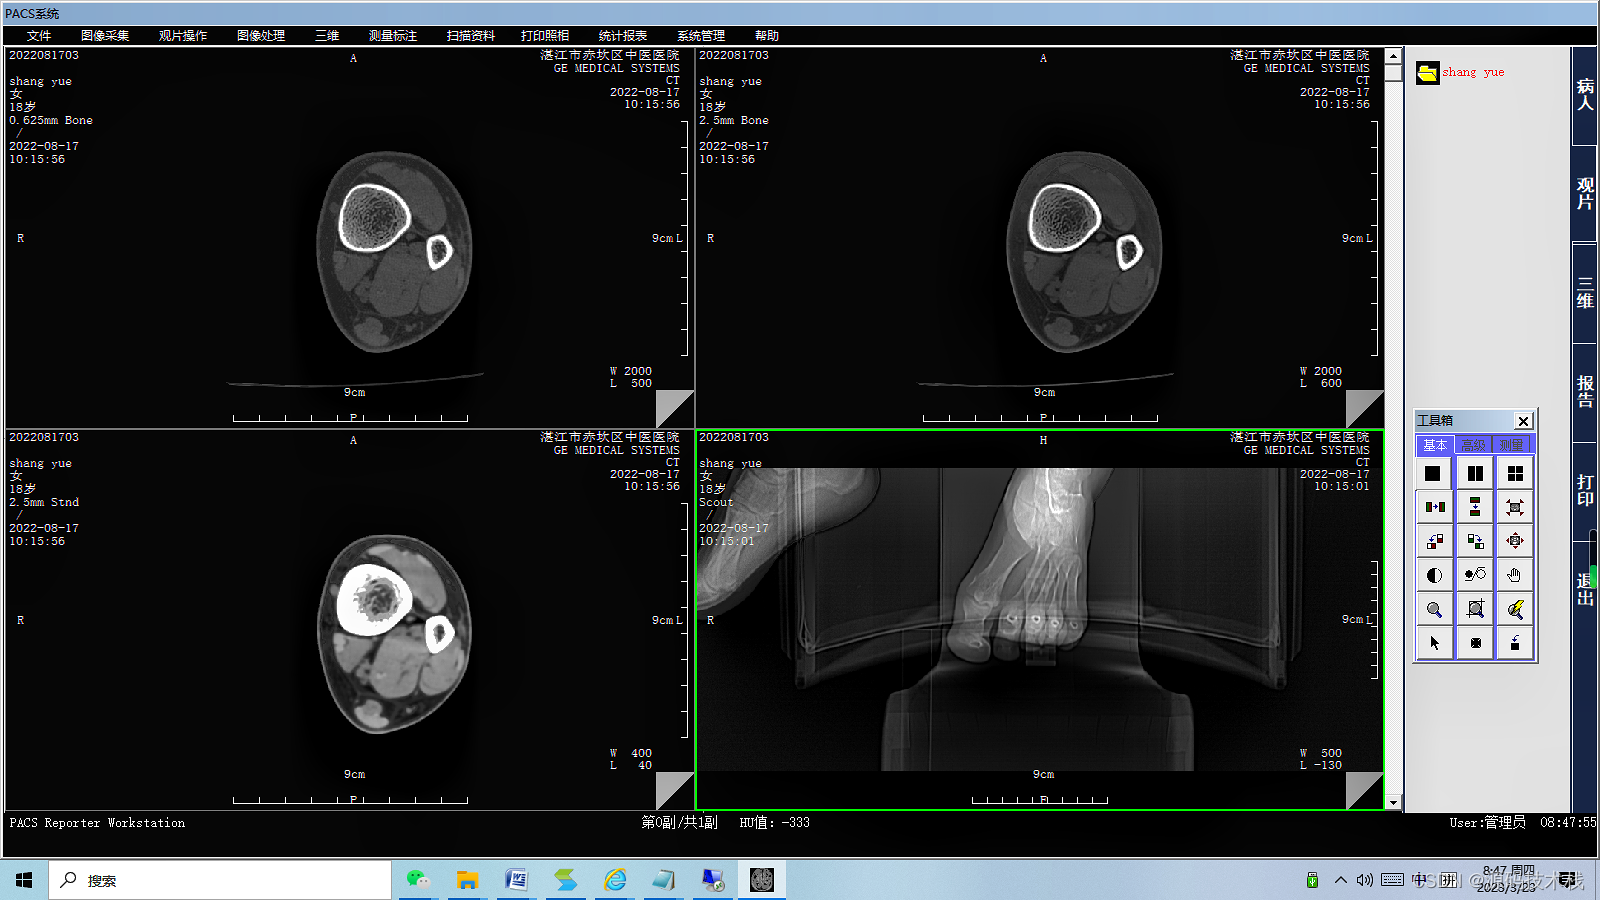

影像查阅

系统采用DICOM和非DICOM格式获取影像数据,以通讯方式采集影像原始DICOM数据;

支持多屏和竖屏显示;支持动态影像电影方式回放、逐帧漫游和冻结;

支持同屏显示多幅影像,自定义显示矩阵;

支持检查模式、比较模式和打印模式的图像显示;

支持多屏显示同一患者的不同序列图像或不同患者的图像;

支持同屏分格显示患者不同体位和不同设备的影像;

支持不同患者间的影像对比。

影像处理和测量功能

系统支持支持窗宽、窗位预设,连续调整窗口准位和直方图,图像均衡、图像平滑处理和边缘增强;

支持对比度调节、正负像旋转、影像黑白反转、影像水平和垂直翻转、灰阶转换和任意角度旋转等;

支持滤波、锐化、播放和彩色绘制等;

支持ROI值、长度、角度和面积等数据测量与计算;

支持数字减影、无级缩放和局部放大;

支持文字和图形标记;查询和保存DICOM头信息;

支持不同影像格式转存;

支持根据检查项目自动应用相应的预设窗宽、窗位。